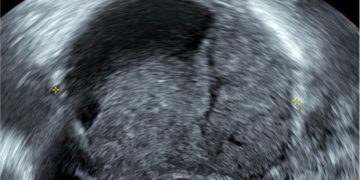

Casi del Mese di Marzo 2023

Cari soci, finalmente online le soluzioni dei casi per il mese di Marzo!!! Grazie a Ilaria Fantasia e Gabriele Saccone!! Caso 1 [pdf-embedder url="https://www.sieog.it/wp-content/uploads/2023/03/caso-clinico-Fantasia-risposta-marzo-2023.pdf" title="caso...